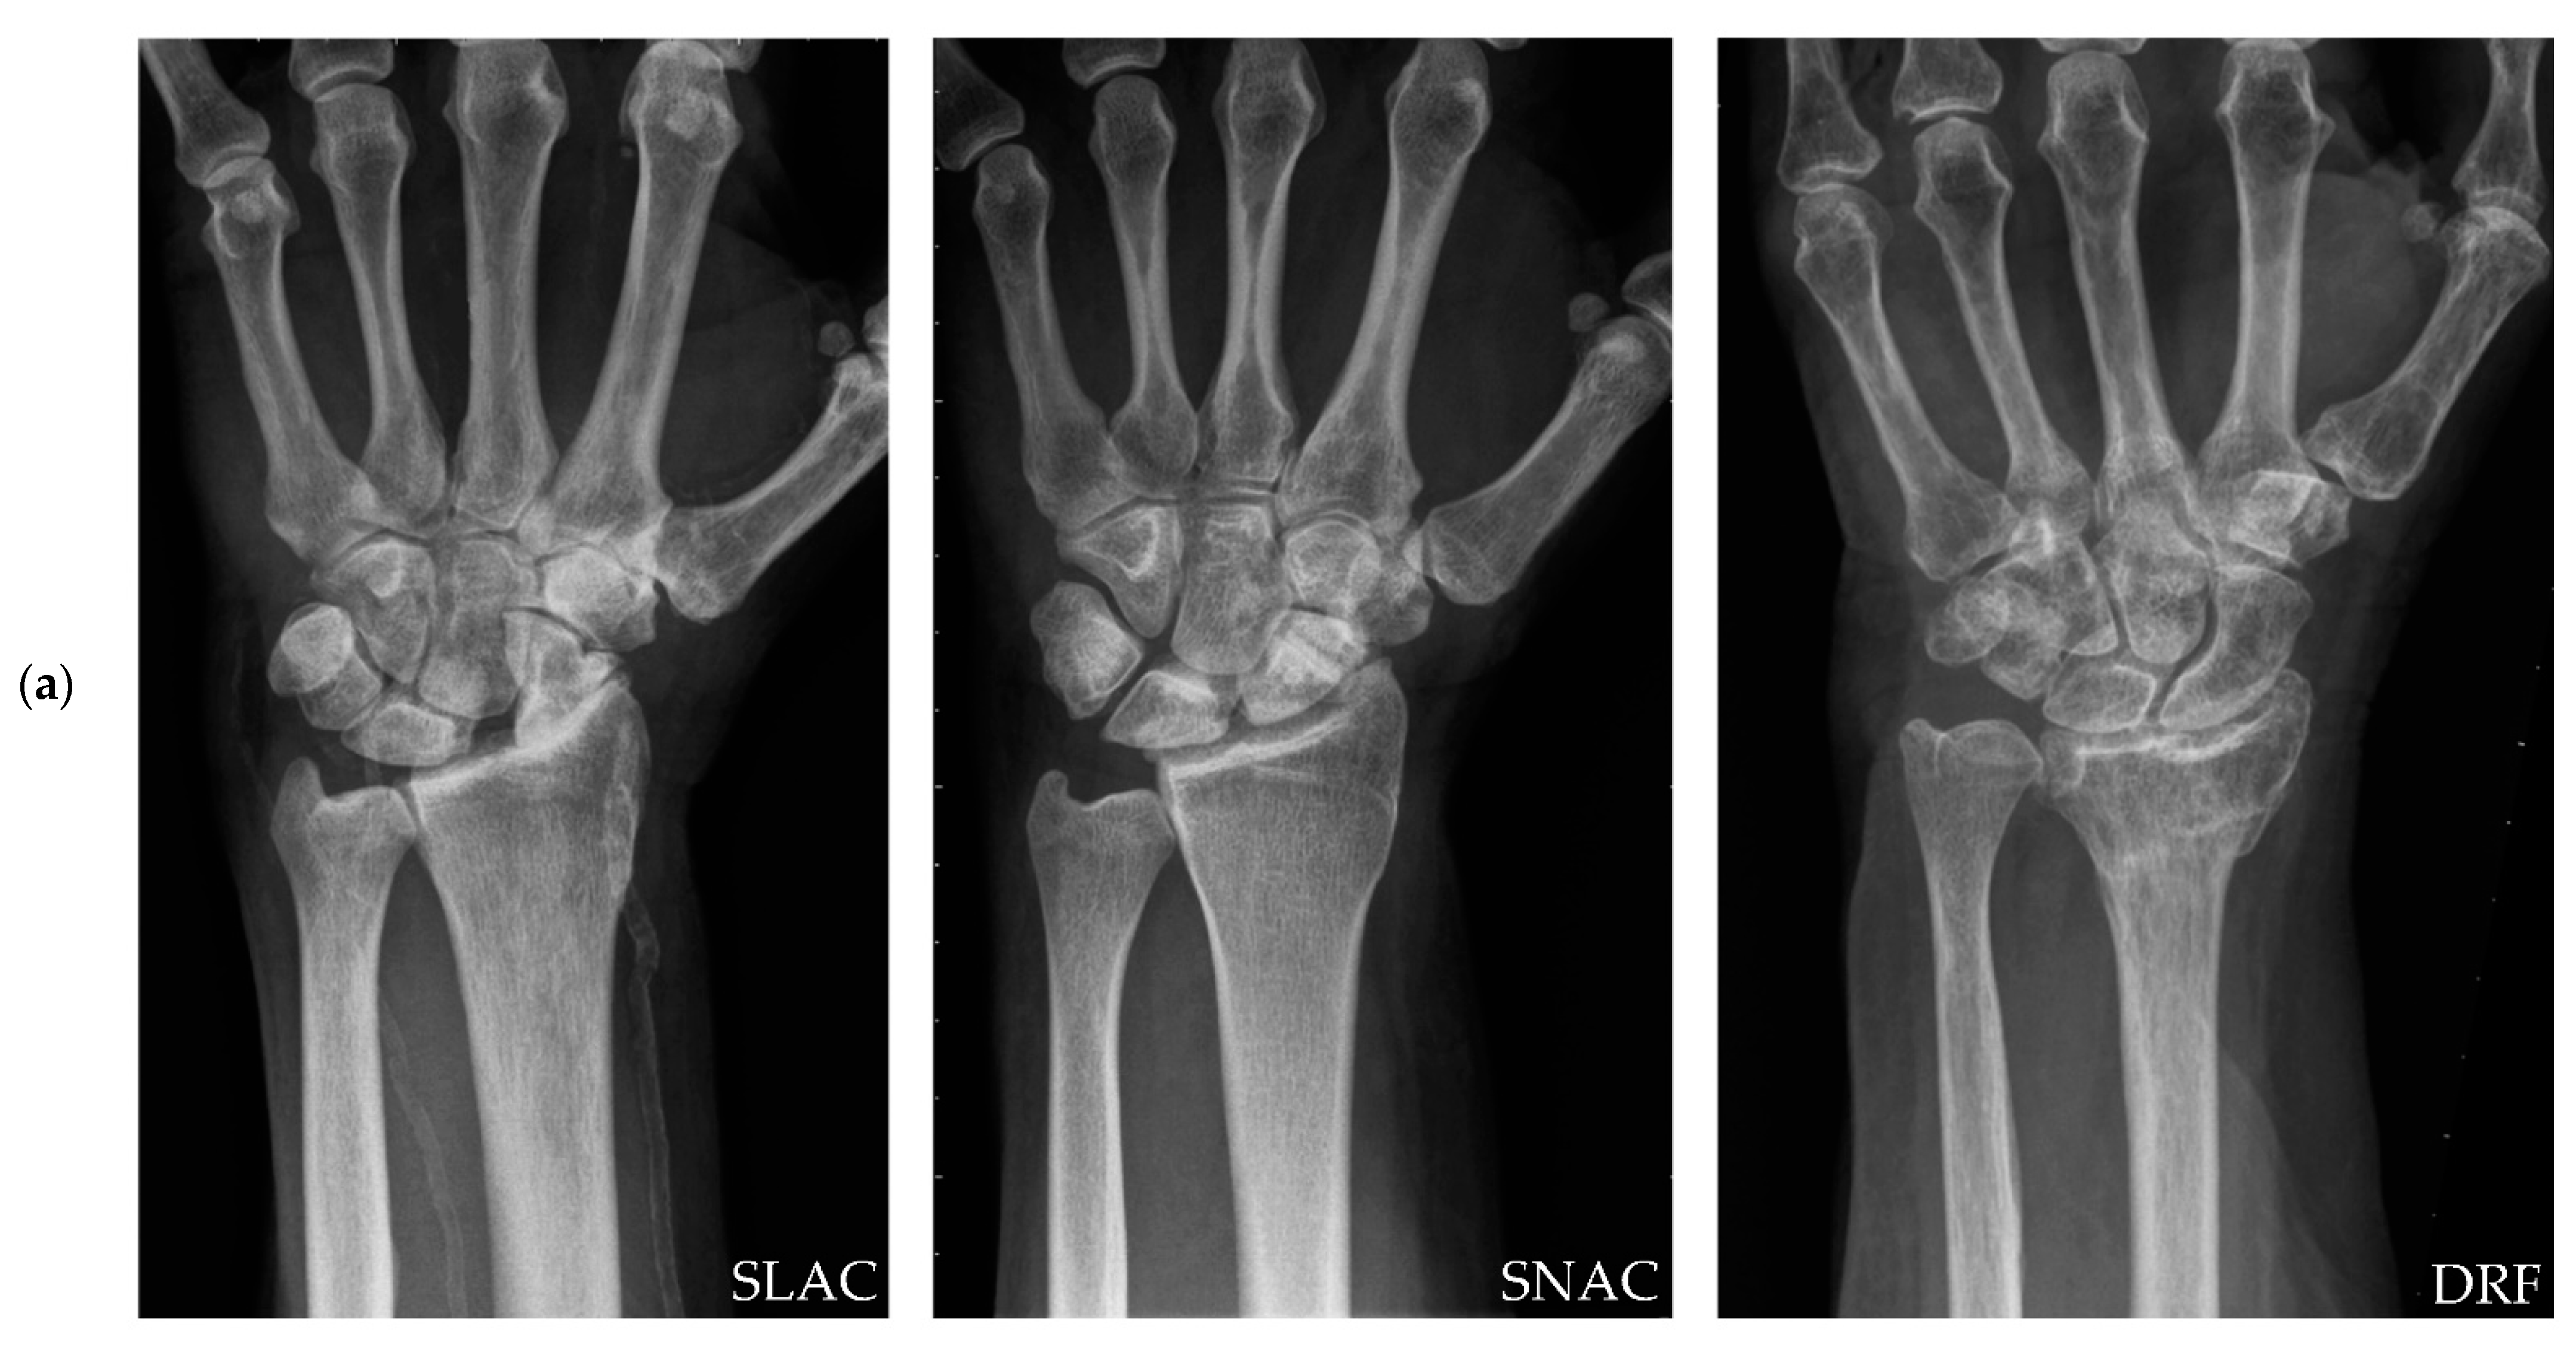

Total Wrist Arthroplasty for Posttraumatic Wrist Osteoarthritis: A Cohort Study Comparing Three Indications

1. Introduction